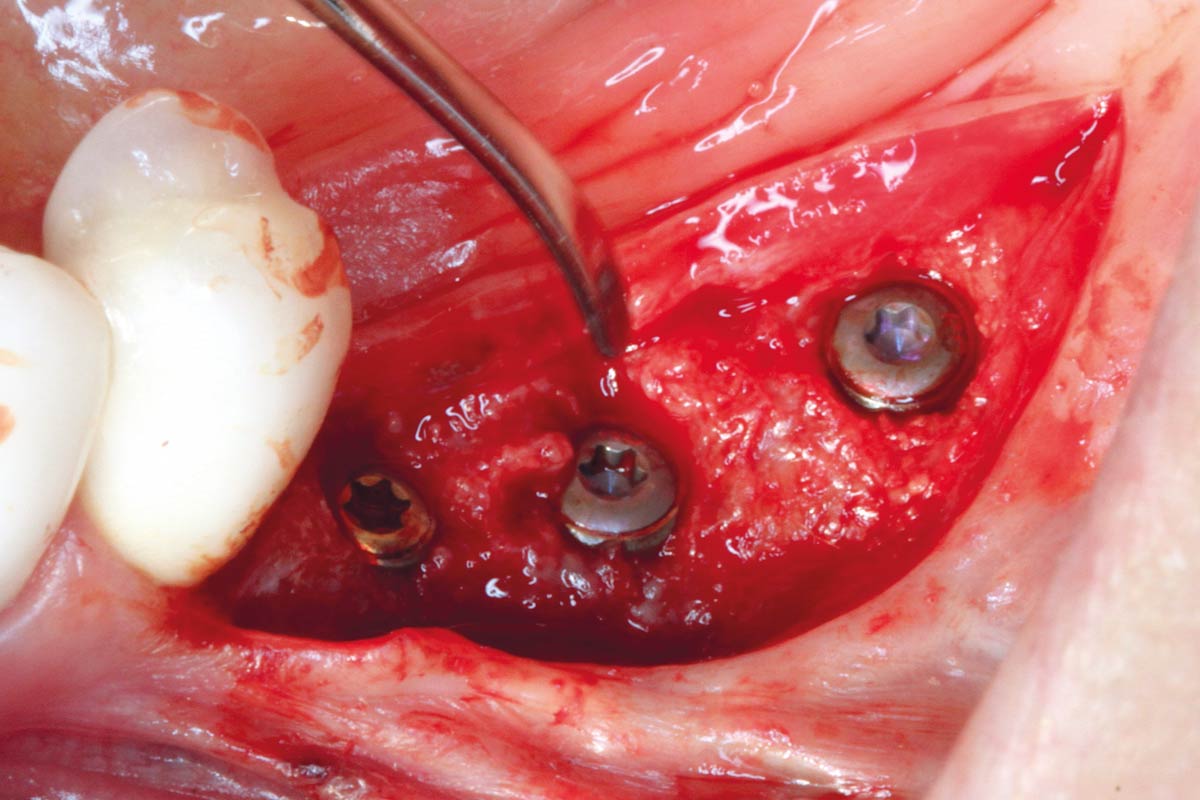

10/12 - Uncovering the implants

Ridge augmentation in the mandible with maxgraft® bonebuilder in a free-end situation - Dr. Dr. Dr. O. Blume